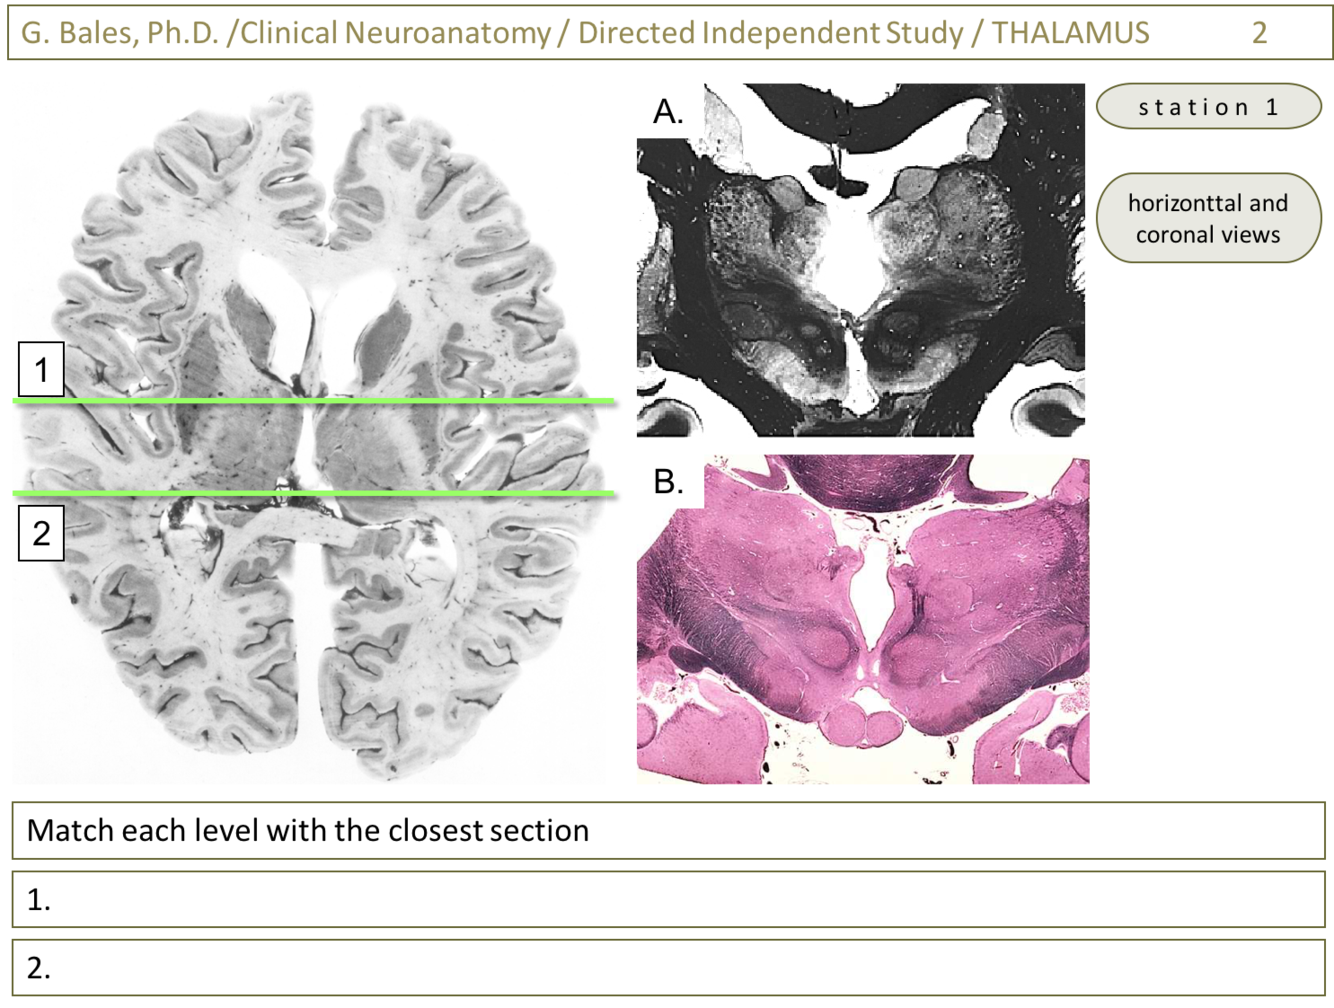

1) A (Thalamus 2-Glass sections; slide 6)

2) B (Thalamus 2-Glass sections; slide 13)